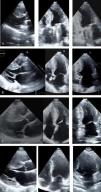

Transthoracic echocardiogram, parasternal long-axis, 4-chamber and 2-chamber views: (A, Case 1): asymmetric hypertrophic cardiomyopathy (HCM) (maximum wall thickness [MWT] 16 mm) and normal prosthetic mitral function; (B, Case 2): asymmetric HCM (MWT 22 mm); (C, Case 3): asymmetric HCM (MWT 21 mm); (D, Case 4): asymmetric HCM (MWT 22 mm).